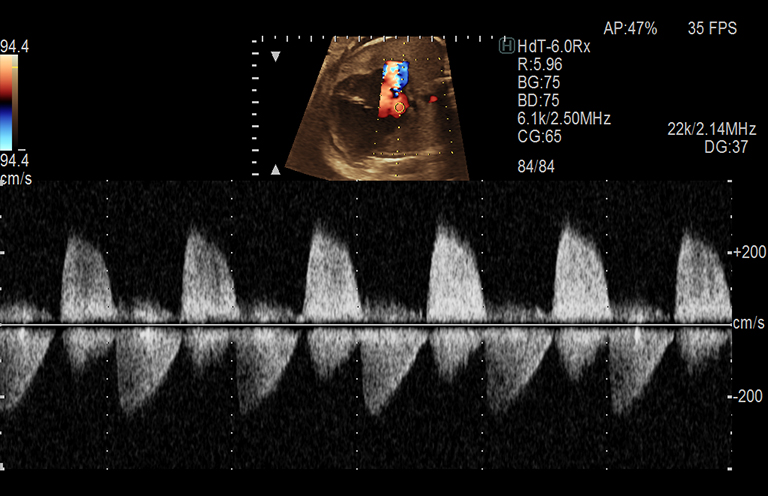

Aplicación: Obstetricia

Función/análisis: CW convexo

Comentarios: Feto (32 semanas)